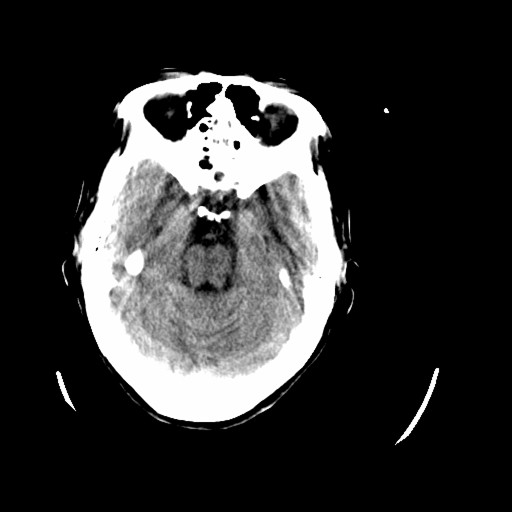

标题: CT16233:女,44岁,智障多年,现感头痛 [打印本页]

标题: CT16233:女,44岁,智障多年,现感头痛

小脑有啥病变?

橄榄桥小脑萎缩.左侧小脑脚腔梗.

为什么不考虑发育畸形呢

1)小脑萎缩。2)小脑蚓部发育不良。

橄榄桥小脑萎缩可能,建议mri进一步检查以进一步排查。

小脑萎缩征,原因待定.

橄榄桥小脑萎缩